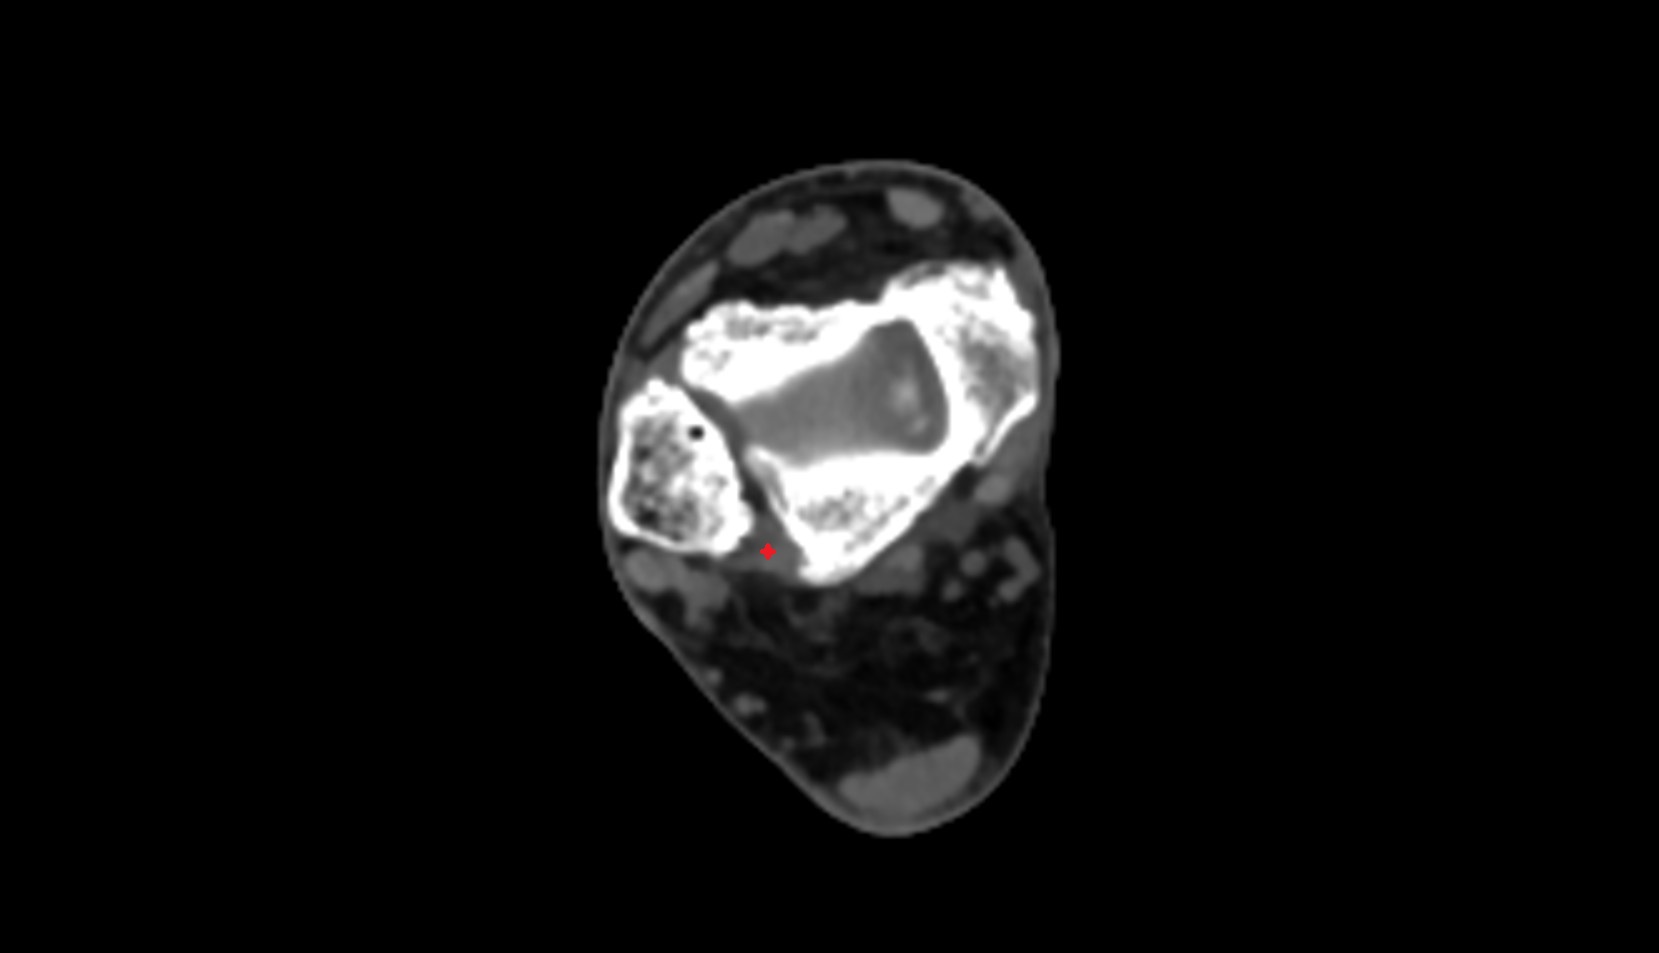

- Ankle joint

- Talocalcaneal joint

- Medial malleolus

- Lateral malleolus